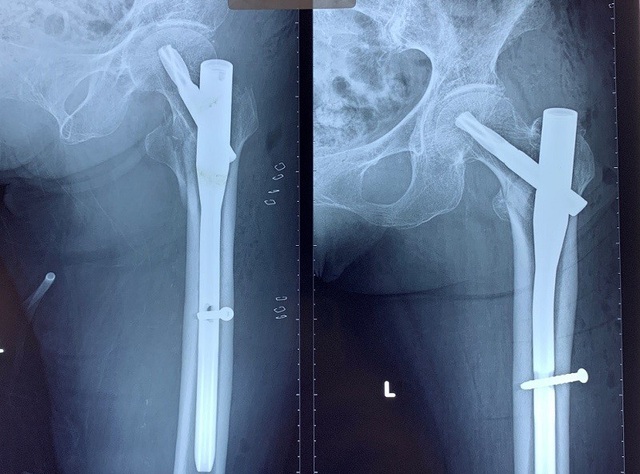

BS Nguyễn Anh Tuấn, khoa Chi dưới, Bệnh viện Chấn thương Chỉnh hình cho hay: Qua thăm khám, chẩn đoán hình ảnh cho thấy, bệnh nhân bị gãy liên mấu chuyển xương đùi trái sau tai nạn sinh hoạt. Trên phim X-quang khớp háng ghi nhận liên mấu chuyển xương đùi bị gãy nhiều mảnh và di lệch khiến bệnh nhân đau nhiều.

Sau hội chẩn, với sự đồng thuận của gia đình người bệnh các bác sĩ đã quyết định thực hiện cuộc mổ cho cụ bà. Trong cuộc phẫu thuật, ê kíp bác sĩ đã mở lòng tủy ở đỉnh mấu chuyển, đặt cờ dẫn từ đỉnh mấu chuyển qua ổ gãy. Khoan tủy, đóng đinh chốt rỗng cố định ổ gãy, bắt vít vào cổ xương đùi.